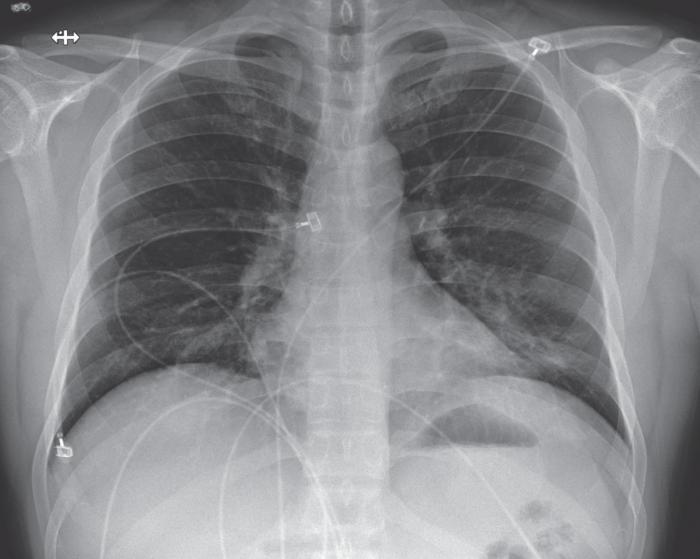

住院第6天(患病第10天),第四次胸部X射线照片显示两肺都有底条索状阴影,这与非典型肺炎相符(图5),听诊时在两肺均有罗音。

前后胸部X光片,2020年1月26日(疾病第十天,医院第六天)。